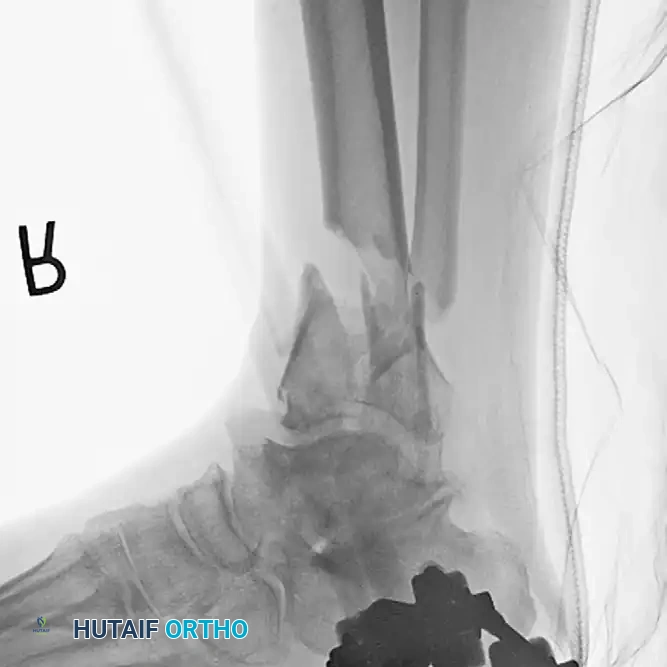

TIBIAL SHAFT Surgical Diagram

Postoperative radiograph demonstrating definitive management with a primary tibiotalocalcaneal arthrodesis using a retrograde intramedullary implant. This construct bypasses the comminution and provides rigid distal fixation.